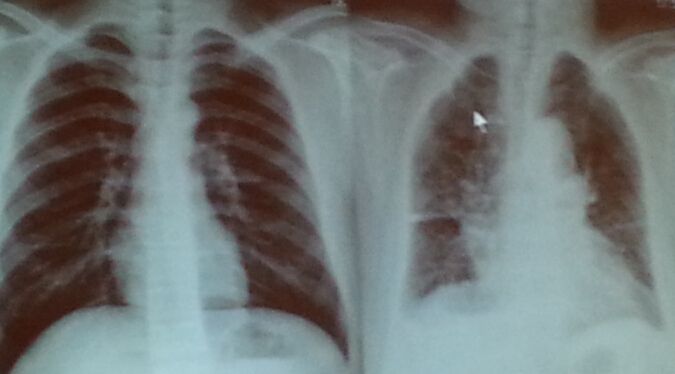

此外,肺部高分辨 CT 也能助一臂之力,肺静脉闭塞病患者常可见纵隔淋巴结肿大、小叶中心型磨玻璃改变及小叶间隔增厚等表现,而IPAH ()HPAH患者相对少见。其中以小叶中心型弥漫性磨玻璃样改变为著。